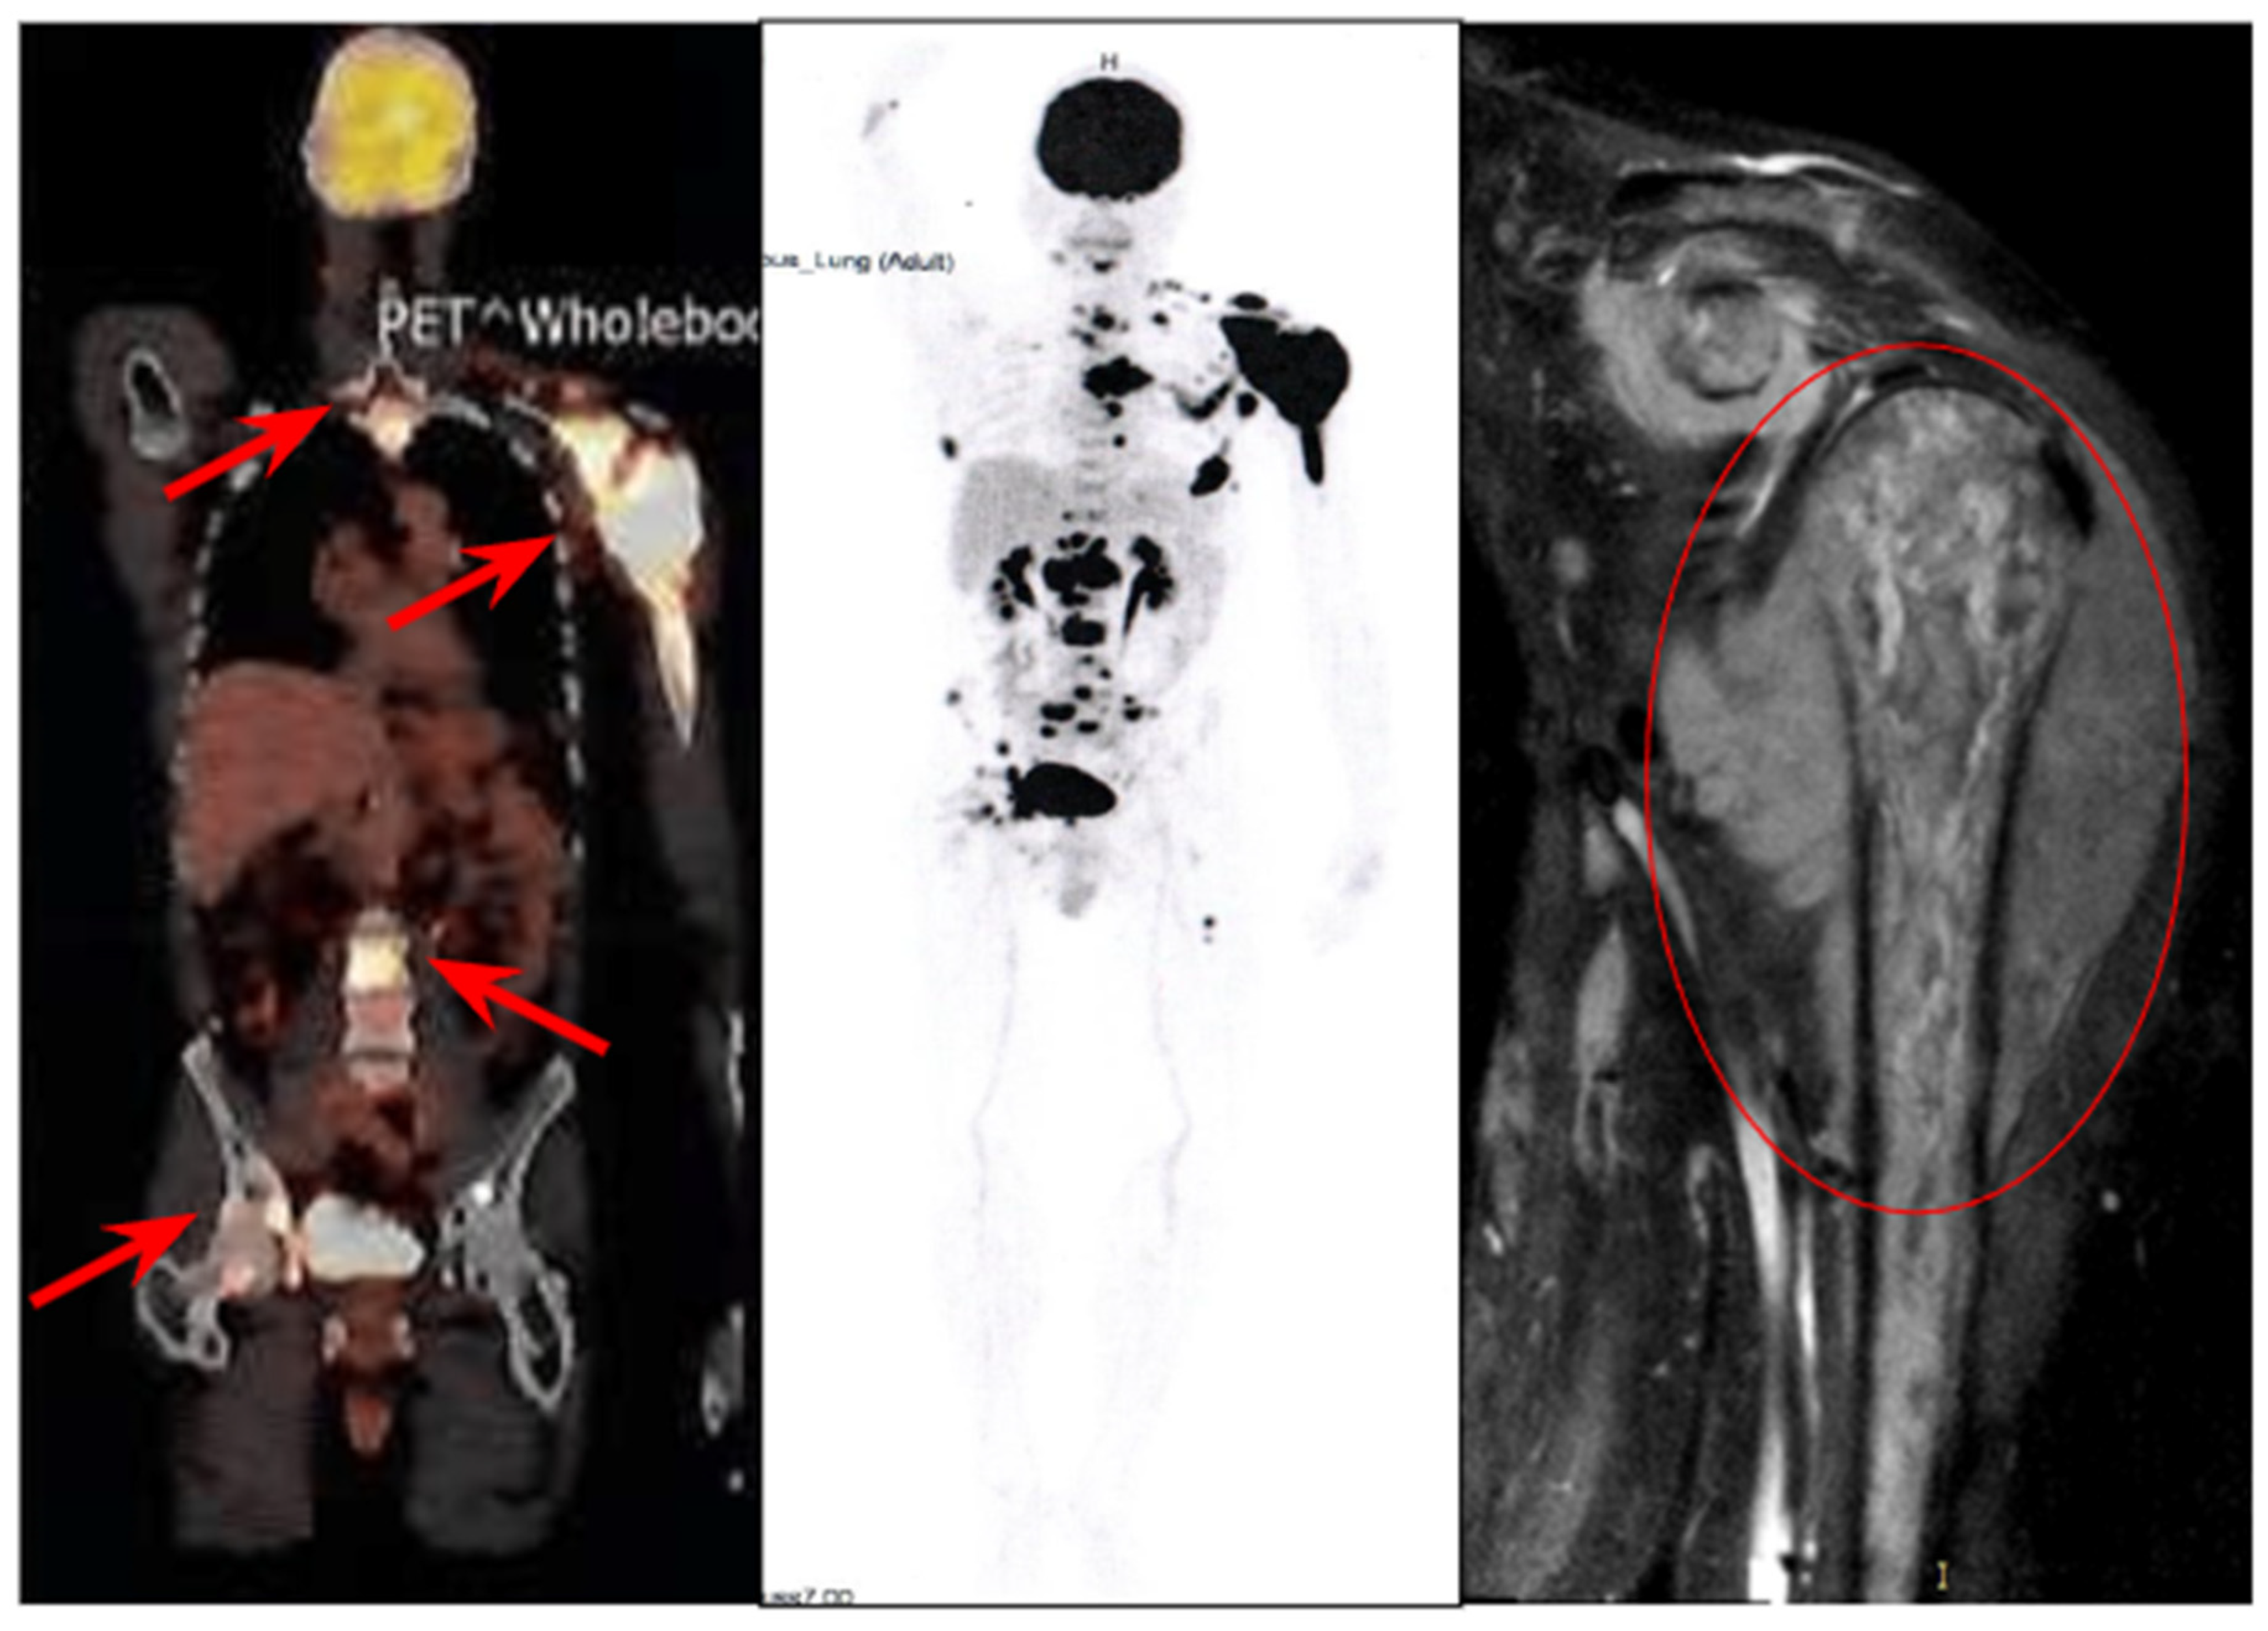

2. Case Report

2.1. History of the Disease and Treatment